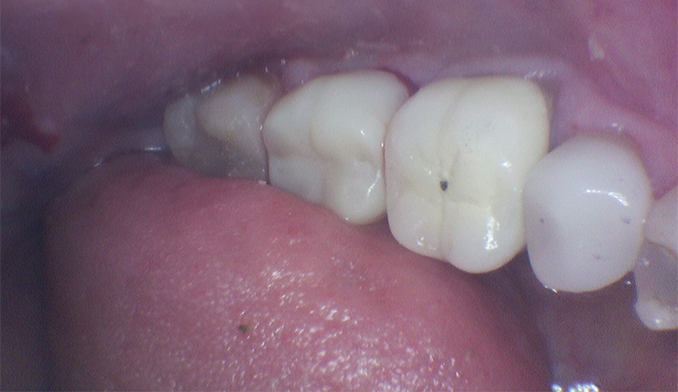

Replacement of Gumline Filling for Improved Esthetics

The patient was unhappy with the appearance of an old filling along the gumline. We replaced it with a new, more natural-looking tooth-colored filling, enhancing the smile’s overall esthetics.